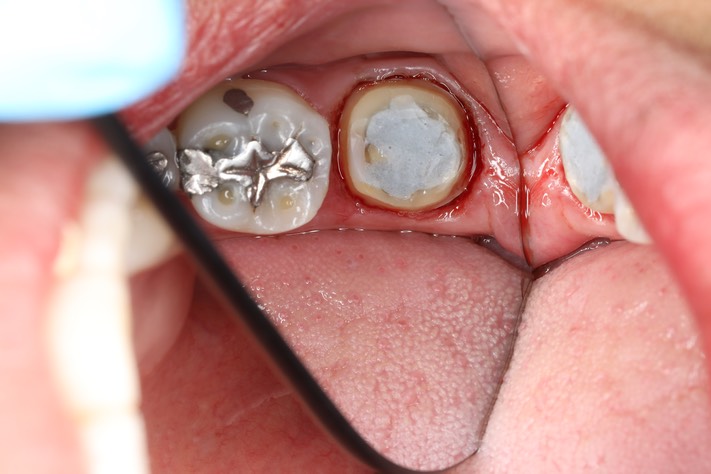

Kris Nip #18 prep